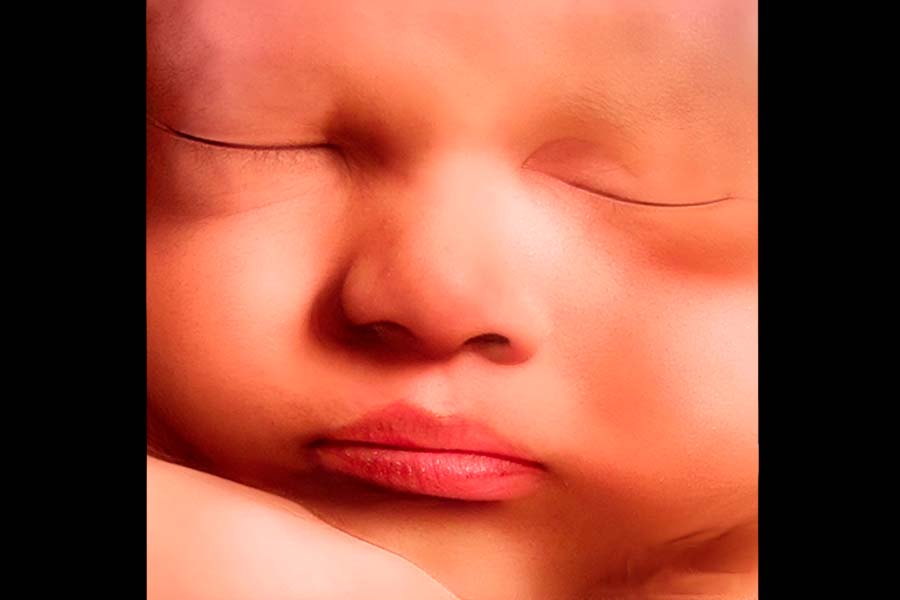

before

after

Con la mejor calidad 8k

Todas las fotos son editadas para obtener el mejor resultado en 8k